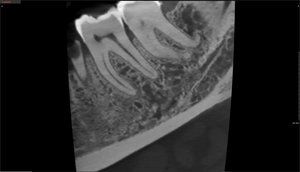

Green X von orangedental Endo Aufnahme

Höchste Detailschärfe

Das Green X ist mit 49μm bei einem FOV von 4x4 cm das Gerät mit einem der weltweit höchsten Auflösungen und der daraus resultierenden Detailschärfe. Dank der byzzEz3D-i Software mit dem Endo-Modul rekonstruiert diese aus ultrahochauflösenden Schichtaufnahmen perfekte 3D Aufnahmen. Diese können dann als Hologramm in allen drei Dimensionen vermessen werden.

Ein ideales Instrument zur Vorbereitung für jede Wurzelkanalaufbereitung und WSR und auch ein hervorragendes Hilfsmittel zur 3D-Visualisierung, Behandlungsplanung und Patientenberatung.

Endo gut - alles gut

Zahnerhaltung ist eine der Hauptdisziplinen in der Zahnheilkunde

Hierzu stehen heute der modernen Zahnheilkunde vielfältige Technologien zur Verfügung, um die Zähne endodontisch zu diagnostizieren. Neben der 2D-Radiologie und Mikroskopie ist die DVT-Technologie das wichtigste Diagnosewerkzeug.

Die byzzEz3D-i Software mit dem erweiterbaren Endo-Modul rekonstruiert aus den ultra-hochauflösenden Schichtaufnahmen perfekte 3D-Aufnahmen. Die 3D-Endo-Aufnahmen können als Hologramm in allen drei Dimensionen vermessen werden. Sowohl die Bi- und Trifurkation, Kanalanzahl, Kanalverlauf, Kanallänge und -durchmesser sowie die Krümmungsradien können einfach farblich gekennzeichnet werden. Damit ist das 3D-Endo-Modul nicht nur ein ideales Instrument zur Vorbereitung für die Wurzelkanalaufbereitung und WSR, sondern auch ein hervorragendes Hilfsmittel zur 3D-Visualisierung, Behandlungsplanung und Patientenberatung.